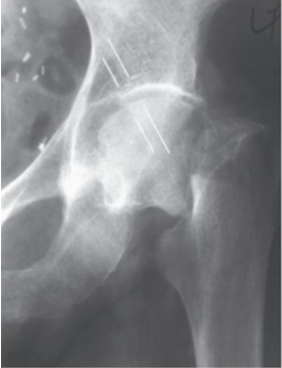

Fractura presente en esta radiografia

Intertrocanterica

Mecanismo de lesion de esta fractura

Jovenes: Alta energia

Ancianos: Caisa simple, impacto directo en trocanter mayor

De acuerdo a la clasificacion de EVANS esta fractura se considera

Inestable

Estable

Tratamiento de fractura intertrocanterica

Idealmente <48hrs post lesion

Clavo endomedular con tornillo deslizante

Tratamiento de fractura intertrocanterica en pacientes con comorbilidades graves

Protesis parcial (De Thompson)